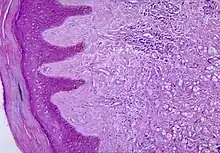

Diagnosis of Lobo's disease is made by taking a sample of the infected skin (skin biopsy) and examining it under the microscope.[4] Lacazia loboi is characterized by "lemon-shaped" fungi, a "sieve-like" appearance due to unstained fungi, and long chains of spherical cells interconnected by tubules.[4]

The cells appear to be yeast-like with a diameter of 5 to 12 μm. Attempts to culture L. loboi have so far been unsuccessful.